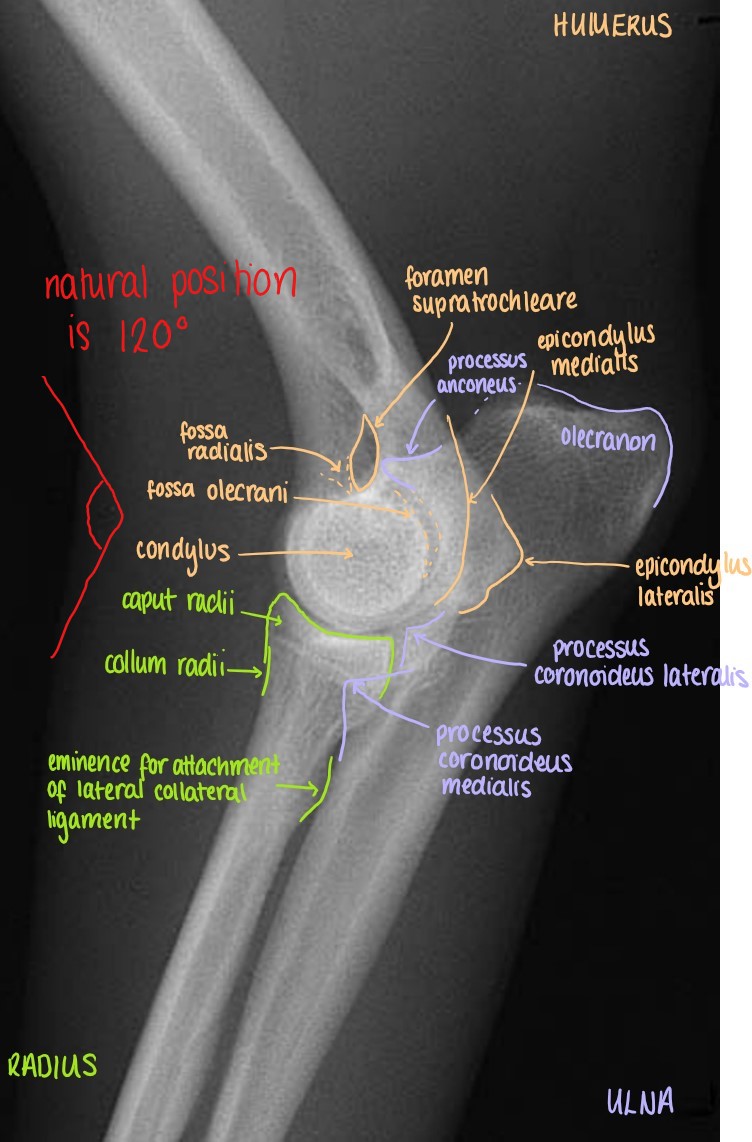

Articulatio Cubiti